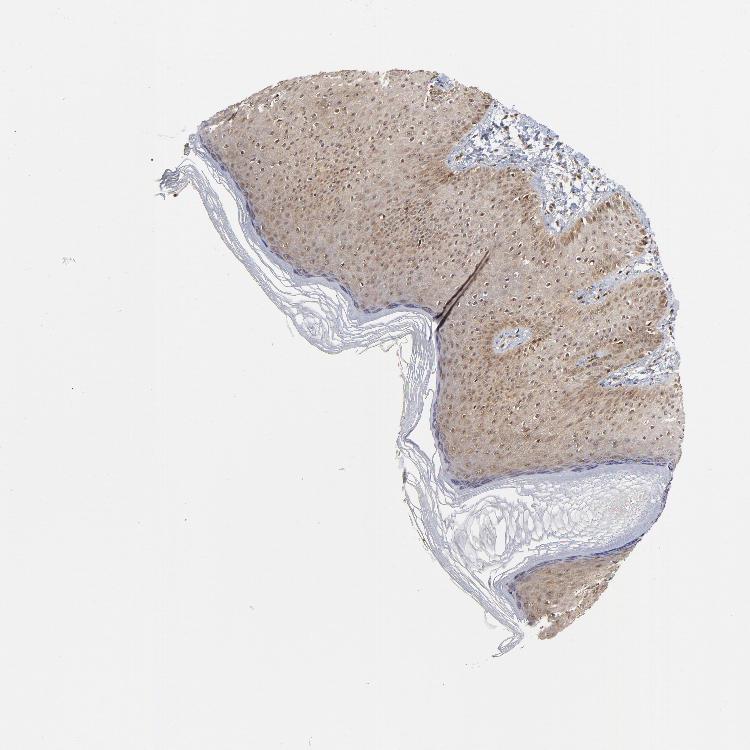

SKIN 1 - Antibody stainingi

Antibody staining in the annotated cell types in the current human tissue is reported as not detected, low, medium, or high, based on conventional immunohistochemistry profiling in selected tissues. This score is based on the combination of the staining intensity and fraction of stained cells.

Each image is clickable and will lead to virtual microscopy that enables deeper exploration of all samples and also displays staining intensity scores, fraction scores and subcellular localization as well as patient and tissue information for each sample.

Antibody HPA003152Antibody HPA003274

Langerhans Not detectedLow

Fibroblasts Not detectedLow

Keratinocytes Not detectedLow

Melanocytes LowMedium

SKIN 2 - Antibody stainingi

Epidermal cells MediumHigh